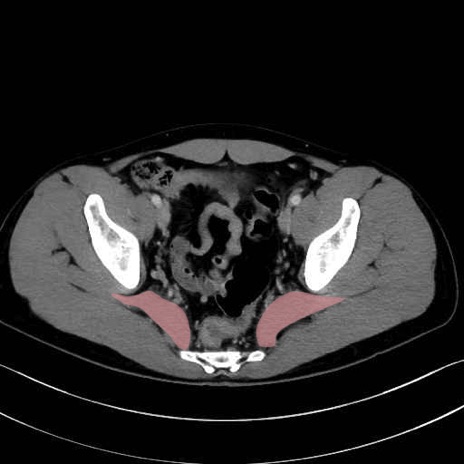

梨状筋 (Piriformis)